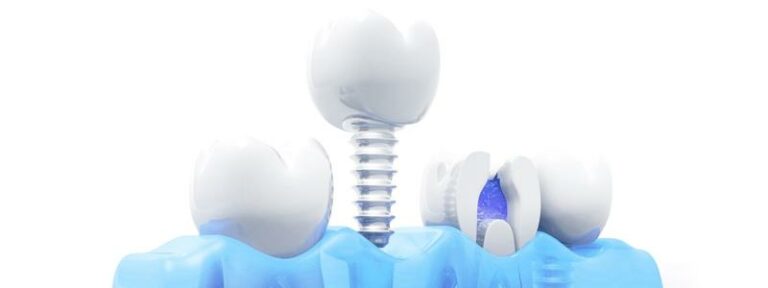

Alles Auf 6 Zahnimplantaten Kosten & Preise 2023

Die Kosten für Zahnimplantate sind in Deutschland unglaublich wettbewerbsfähig. Viele Kliniken bieten eine Vielzahl von Paketangeboten, die Ihrem Budget entsprechen. Wenn Sie beispielsweise mehrere Implantate